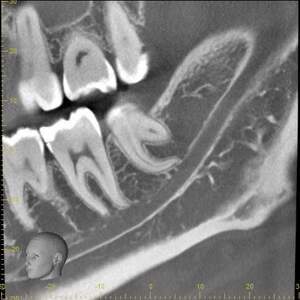

CT

CTで親知らずと神経(下歯槽管)の位置を確認しました。

親知らずと神経は一定の距離があり、麻痺などのリスクがほとんどないと判断できます。